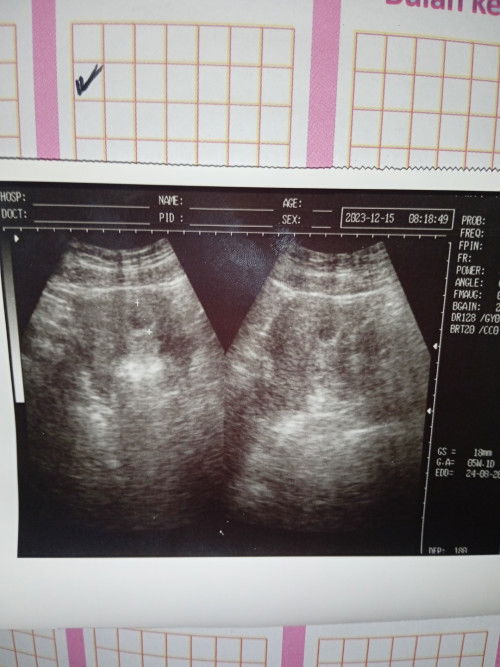

Bunda semua saya udh 3 kali usg. Dari 3 3 nya semua usia janin beda 2 mingguan dari hpht. Hrsnya skrng 22 week 5 hri klu dri hpht, Trnyta klu usg baru 20 week 5 hri, dan sebelumnya juga gitu tiap usg mundur 2 minggu. Jdi skrng utk hpl itungan nya ngikut usg aja ya dri pda hpht? Usg pertama di usia 5week. #SeriusTanya

Bun usia janin itungan nya lebih akurat hpht atau usg ? Aku klu hpht udh 18 week 1 hari, Klu usg 16 week 1 hari. Beda 2 minggu. #Sharing_dong_Bund Mau usg pengen lihat JK kira2 udh kelihatan di minggu brpa y ?

Bunda bunda semua ada ga yg hpht 26 oktober, kan klu di apk minggu 7 hari 1, Nah tadi berhubung q udh ada jadwal buat usg, tadi q usg dan di usg masih 5-6 minggu dan baru kelihatan kantung nya ? Apa wajar ya dn bisa berkembang lgi. Maaf ya cmn worry aja krena ini di nanti2 g pernat telat minum asam folat+susu juga nggk nge flek jga. Dr nya sih klu dri hpht bilang nya hrs sdh ada. #seriusnanya

Minggu 6-7 apa udh ada janin nya ya ? Ini aku #minggu ke7 mau usg, kira2 udah kelihatn belum ? Soalnya q obesitas juga